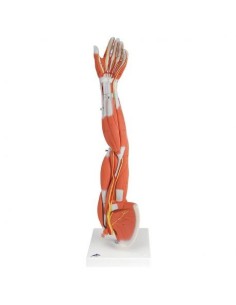

Esplora la nostra collezione dei migliori modelli anatomici degli arti superiori ed inferiori

La nostra esclusiva selezione di modelli anatomici delle estremità, meticolosamente prodotti dai leader del settore 3B Scientific ed Erler Zimmer, offre una rappresentazione fedele e dettagliata delle complesse strutture di mani e piedi. Questi modelli sono fondamentali per chiunque desideri esplorare l’anatomia delle estremità con una precisione senza pari, rendendoli strumenti didattici ideali per l’educazione e la pratica in ortopedia, fisioterapia e medicina dello sport.

Ortopedici, fisioterapisti, studenti di scienze della salute e istituti educativi si affidano ai nostri modelli per le loro esigenze educative e professionali, utilizzandoli per dimostrazioni pratiche e per migliorare la comprensione della meccanica e della funzione delle estremità umane.